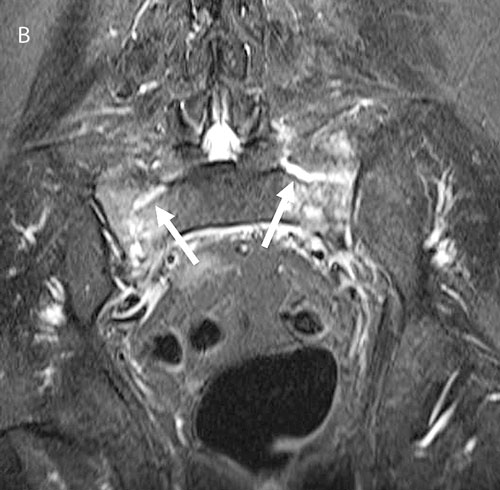

Figur 2. En 65-årig kvinna som behandlades med högdos kortikosteroider för polymyalgia rheumatica hade sedan 2 veckor fått tilltagande smärtor i ländryggen. Smärtorna strålade ned i båda benen, och hon hade mycket svårt att gå. I övrigt inga neurologiska fynd. Röntgen ländrygg (A) visade ingen kotkompression, utan endast degenerativa förändringar. Patienten fick accentuerande smärtor som krävde inläggning 1 vecka senare. MRT ländryggsöversikt (B) utfördes. Denna visade högsignalerande områden (pilar) bilateralt i sakrum förenliga med insufficiensfraktur, vilken också kunde verifieras med datortomografi (C).